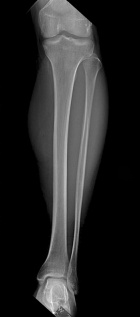

42 year old male presents with c/o L leg/calf pain that is worse with activity for the past year.